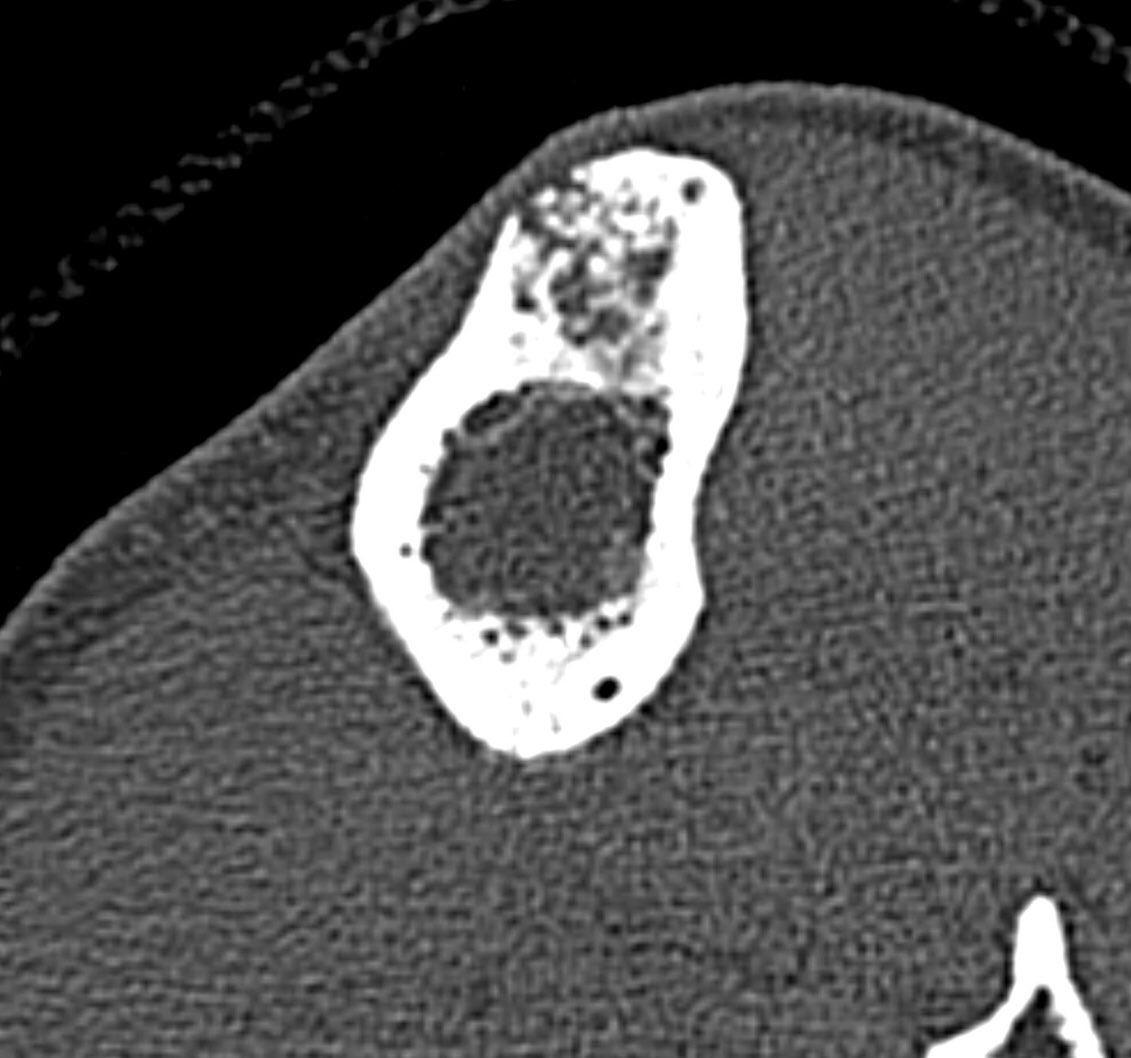

A single destructive lesion or multifocal tumour,may be identified, affecting cortex and often extending to the medulla,most commonly in the mid-tibial shaft.The lesion is typically eccentric and may cause mild bone expansion,endosteal scalloping and eventually destroy the cortex

AD typically appears multilocular and trabeculated, with intervening and surrounding sclerosis. A distinct periosteal reaction is unusual. An extra-osseous mass and pathological fracture may be seen

The tumour in the current case appeared to have arisen in the anterior cortex, extending inferiorly into both cortex and medulla, as a single focus of disease. The trabeculated appearance on radiographs appears to reflect the unusual extension of tumour through tibial cortex.

, with preservation of vertical ridges of cortical bone, surrounded by tumour, adjacent to areas of marked cortical thinning. Oedema-like hyperintensity on the bone surface suggests imminent fracture